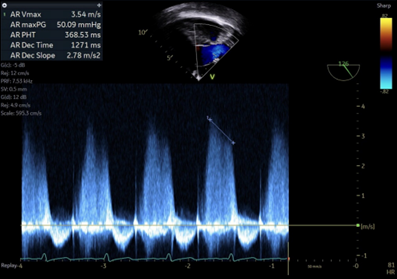

5.  Based on the pressure half time of 368ms in image 6, what is the severity of the residual aortic regurgitation?

A pressure half-time (PHT) of 368ms indicates moderate aortic regurgitation.  Pressure half time is a measure of the speed of equalization of pressures between the aortic and left ventricular pressures in diastole.  More specifically, PHT is the time it takes for the pressure gradient between the aorta and left ventricle to reach half its original value. More regurgitation allows for more rapid equalization of these pressures. PHT in mild regurgitation is >500ms, in moderate regurgitation is 500-200ms, and in severe regurgitation is <200ms.